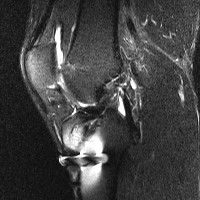

무릎 mri 간단히 봐주실 수 있으시나요 ㅠㅠ

안녕하세요 8년전 십자인대 수술하고 최근 무리한 운동에 무릎 불편감이 생겨서

mri 찍었습니다.

진단결과는 첫 찍은 병원에서 활액막염 이라는 진단을 받았습니다. 혹시 봐주실 수 있으실까요?

올라온 MRI가 단편적이라서 정확한 진단에 어려움이 있지만 십자인대에는 큰 이상이 있지는 않은것 같으며, 무릎관절내 물이 있는 것으로 보아 활액막염의 진단이 맞을 것 같습니다.

하지만 단편적인 영상이기 때문에 촬영병원에서 정확한 판독지 등을 받으시는 것이 좋겠습니다.